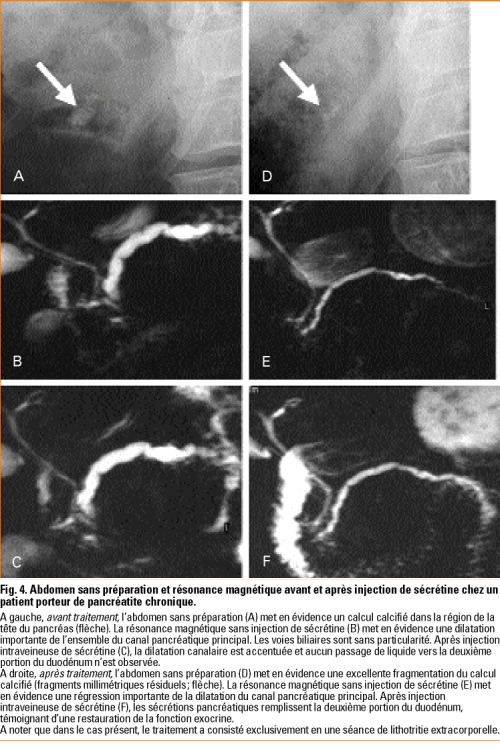

Traitement Endoscopique De La Pancreatite Chronique Revue Medicale Suisse